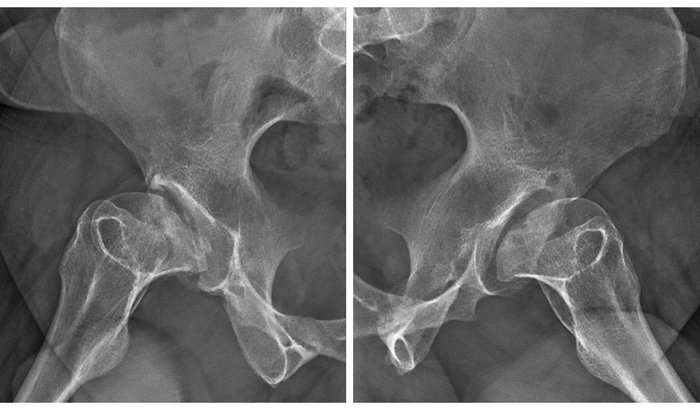

O procedimento indicado é uma artroplastia total bilateral dos quadris, por causa de uma artrose severa. Essa cirurgia vai me devolver qualidade de vida e me permitirá continuar fazendo o que mais amo: levar alegria e risadas para as pessoas.